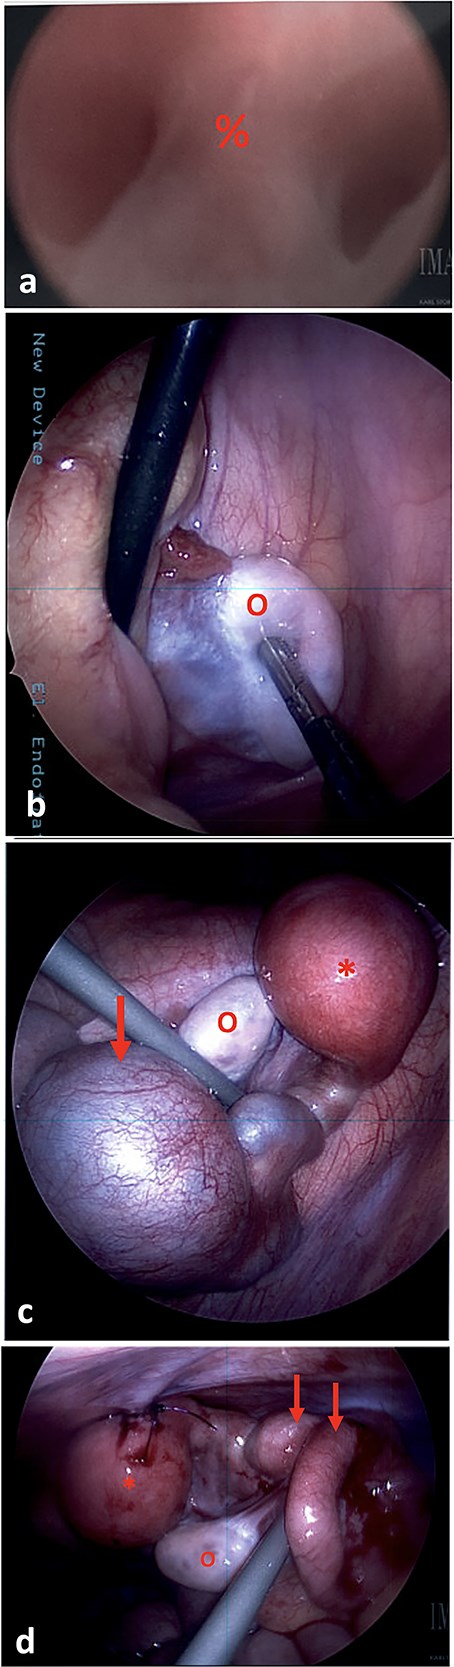

(a) On vaginoscopy, a central septum (%) was noted, suggestive of a longitudinal vaginal septum or hemi-vaginas. (b) Laparoscopic photograph showing the left ovary (o) located in the left lower pelvis, not attached to any tubal structure. (c) Laparoscopic photograph demonstrate a right-sided hypertrophic uterus (*), significantly dilated and firm due to retained blood, and a markedly dilated and tortuous right fallopian tube (arrow). The right ovary appeared normal (o). (d) The uterine dome (*) was sutured to the abdominal wall. The right fallopian tube was decompressed after aspiration (arrows).

During diagnostic laparoscopy, 50 ml of clear serous fluid was aspirated from the pelvic cul-de-sac. A left ovary was present in the left lower quadrant, but no left sided uterine or tubal structures were identified (Fig. 2b). On the right side, a hypertrophic hemiuterus was visualized, significantly dilated and firm due to retained blood (hematometra) (Fig. 2c). The right fallopian tube was markedly dilated and tortuous with a cystic dilation at the mid portion consistent with hematosalpinx. The right ovary appeared normal. No intrabdominal vaginal structures were noted.